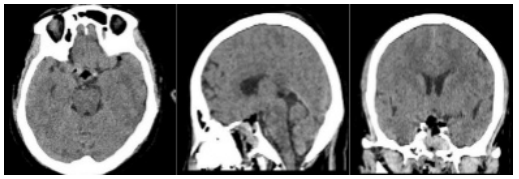

⑤术后复查 肿瘤全部切除,术区无渗血。

本患者肿瘤位于鞍内及鞍上区域,呈囊实性,与下丘脑粘连紧密,伴钙化明显,视神经、垂体柄受压移位明显,毗邻重要神经血管结构,手术难度较高,术中早期瘤体中心减压可以为肿瘤的包膜外分离提供空间,尤其是一些囊性成分的减压。对蛛网膜平面进行锐性和轻柔的分离是非常重要的,可以避免供应视交叉的垂体上动脉分支血管的损伤。术中选用成角内镜可以进一步观察和切除直视下难以到达的角落里的残余肿瘤。术前通过影像学表现判断垂体柄的位置,术中根据垂体柄与肿瘤的关系,尽可能多地或完整地保留垂体柄,可减轻术后尿崩症的发生率。本患者术中视神经、垂体柄、穿支血管保护完好,肿瘤完全切除,术后患者视力下降、乏力等症状明显改善,无垂体功能低下、脑脊液鼻漏、颅内感染等并发症,患者生活质量得到很大改善,患者家属满意度较高。目前,经鼻蝶微创手术成为颅咽管瘤的主要手术方式,减少手术创伤,缩短手术时间及住院时间,也为患者降低了经济负担。